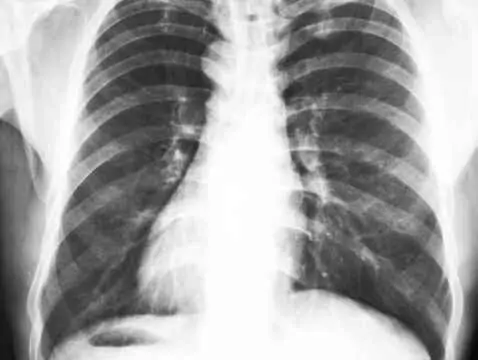

Parmi les malformations congénitales les plus courantes chez les nouveau-nés et les enfants figurent les malformations du cœur et de l'appareil circulatoire. Une malformation cardiaque congénitale...

Les malformations cardiaques congénitales touchent 7 à 8 enfants nés vivants sur 1000 et sont responsables d'environ 20 % des décès dans ce groupe d'enfants. Dans la plupart des cas, la cause de la...

Dans la plupart des cas, les malformations cardiaques congénitales sont diagnostiquées chez les enfants après la naissance. Certaines d'entre elles ne provoquent aucun symptôme pendant longtemps,...